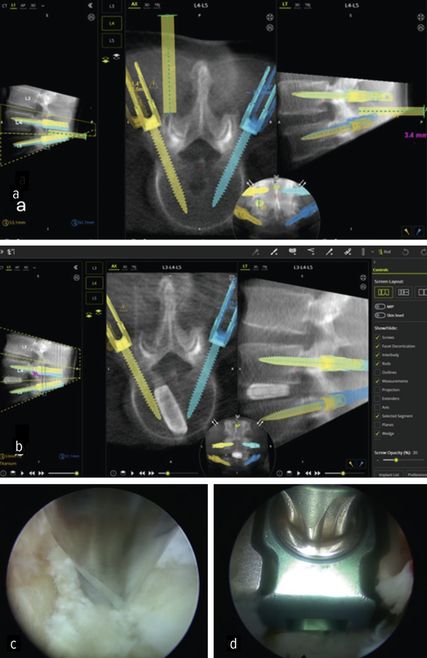

Lumbale interkorporelle Fusion

Die minimalinvasive transforaminale lumbale interkorporelle Fusion (Minimally Invasive Transforaminal Lumbar Interbody Fusion; MIS-TLIF) hat in den letzten Jahren an Bedeutung gewonnen, die aufgrund des geringeren Gewebetraumas mit einer früheren Rekonvaleszenz verbunden ist.24 Aus den gleichen Gründen rückt die endoskopische transforaminäre Interbody Fusion (Endo-TLIF) in den Fokus der Aufmerksamkeit. Endo-TLIF ist eine Erweiterung der MIS-TLIF und erfordert eine unilaterale Resektion des Facettengelenkes. Die Grund- und Deckplattenpräparation gilt als entscheidender Faktor, der die Fusionsrate beeinflusst.24 Die Möglichkeit, unter klarer endoskopischer Sicht die Endplatten präzise darzustellen, erlaubt eine ideale Aufbereitung des Fusionsbettes. Dies könnte zu einer Erhöhung der Fusionsrate beitragen. Zudem profitieren die Patienten durch eine raschere Erholung, einen geringeren Opioidbedarf, eine frühzeitige Mobilisierung und eine verkürzte stationäre Verweildauer.25 Limitationen liegen aktuell bei höhergradigen Listhesen und kollabierten Bandscheibenräumen vor.26 Um das Potenzial der Methodik zu untermauern, bedarf es robuster Studien mit erhöhtem Evidenzlevel sowie eines einheitlichen Standards der endoskopischen Fusionstechniken. Abbildung 6 zeigt eine Planungsanwendung (MazorX® Application, Fa. Medtronic) für Endoskoptrajektorie und Pedikelschraubenimplantation im Rahmen der Endo-TLIF-Operation (a, b). Abbildung b zeigt einen oblique eingebrachten Cage (eFuse® expandable, Fa. Evospine), Abbildung c einen Nukleusresektor (Fa. RIWOspine) bei Präparation des Fusionsbettes. Abbildung d zeigt, dass eine Cagedistraktion unter direkter Sicht möglich ist.

Um die Lernkurve in der ESS abzukürzen, wurden in der jüngeren Zeit Versuche unternommen, Navigationssysteme in die ESS zu integrieren. Navigation liefert hochpräzise intraoperative Echtzeitdaten zur Anatomie und bietet exakte Führung bei der Platzierung der Instrumente, die mit herkömmlicher (2D-)Fluoroskopie nicht erreichbar sind.29 Intraoperative Computertomografie und darauf basierende Navigationssysteme stellen eine sichere und effektive Alternative dar. In der konventionellen Wirbelsäulenchirurgie ermöglicht die intraoperative O-Arm-Navigation eine hohe Genauigkeit bei der Pedikelschraubenplatzierung und reduziert Komplikationen.30 Navigationssysteme unterstützen in der ESS die Bestimmung von Trajektorie, Inzisionspunkt und Instrumentenlage und tragen so zur Verkürzung der Lernkurve bei.31,32

Quillo-Olvera et al. zeigten, dass die intraoperative Navigation die Sicherheit der Pedikelschraubenfixation und die präzise Endoskoppositionierung bei TLIF verbessert.33 Klassische Navigationssysteme erfordern optische Marker, die im Operationsgebiet zusätzlichen Platz benötigen. Dieser Einschränkung kann unter Verwendung elektromagnetischer Navigationssysteme (EMN) bei vollendoskopischen Verfahren begegnet werden.33 Randomisierte Studien mit EMN weisen eine geringere Strahlenbelastung und signifikante Reduktion der Operationszeit auf.34 Zukünftig bieten diese Systeme das Potenzial, die Sicherheit zu erhöhen und gleichzeitig die Lernkurve abzukürzen. Abbildung 8 zeigt ein intraoperatives Setup während Endo-TLIF-Operation mit integriertem O-Arm (Fa. Medtronic), navigationsgestütztem Robotersystem (MazorX®) und Endo-Turm mit Funktionseinheiten (Fa. RIWOspine) (a, b). Darüber hinaus illustriert sie eine transforaminäre Diskektomie unter Verwendung des elektromagnetischen Navigationssystems (RIWOtrack®, Fa. RIWOspine) mit Abbildung des Multipads zur Instrumentenkalibrierung (c), EMN mit dargestellten Referenzmarkern und Endoskopiebild (d).

Robotergestützte Chirurgie

Höhere Genauigkeit, kürzere Krankenhausaufenthalte und geringere Strahlenexposition sind die Gründe für den Einsatz bei der Pedikelschrauben-Implantation.32 Zusätzlich bieten sie den Vorteil der exakten physischen Führung, um präoperativ geplante chirurgische Trajektorien in der Endoskoppositionierung umzusetzen. Wang et al. setzten robotische Assistenz bei vollendoskopischen lumbalen Diskektomien ein und konnten Sicherheit und Effektivität als Alternative zur konventionell fluoroskopischen ESS bestätigen.38 Im eigenen Haus wurde das Verfahren bei der endoskopischen TLIF-Operation angewandt.